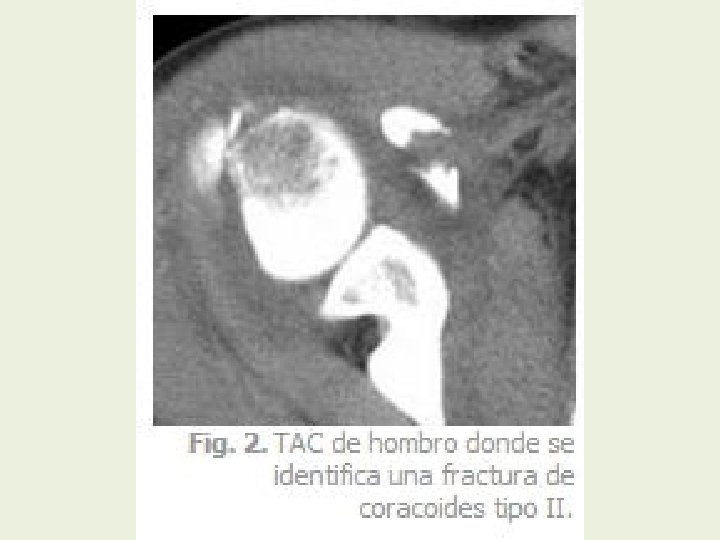

Anatomía de Hombro a través de TAC y RMN